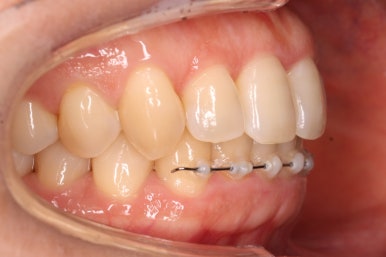

점점 가지런해지고 있습니다.

아랫니는 원래 바깥으로만 교정하기로 했는데, 더 정교한 마무리를 위해서 설측으로도 장치를 부착했습니다.

조금만 더 정리를 하고 마무리를 하기로 하였습니다.